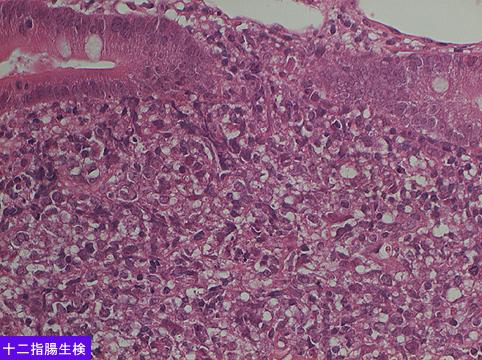

A case of MLP (multiple lymphomatous polyposis) type malignant lymphoma in which multiple lesions developed in the stomach, duodenum, and large intestine.

Malignant Lymphoma/MLP type

Duodenum/First portion, bulb

Histology